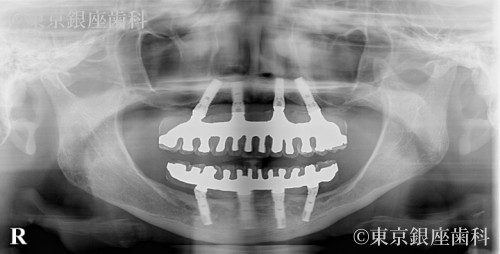

長年の入れ歯生活から自分の歯のように噛める喜びを取り戻した50歳代男性のインプラント症例

若い頃から入れ歯を使用し噛めない・笑えない悩みを抱えていたが、上下インプラントで噛み合わせと表情が改善。再手術も経て安定している。

上下ワンデイインプラント(再オペあり)

腫れ・痛み・出血、骨結合不全、長期脱落、再手術の可能性